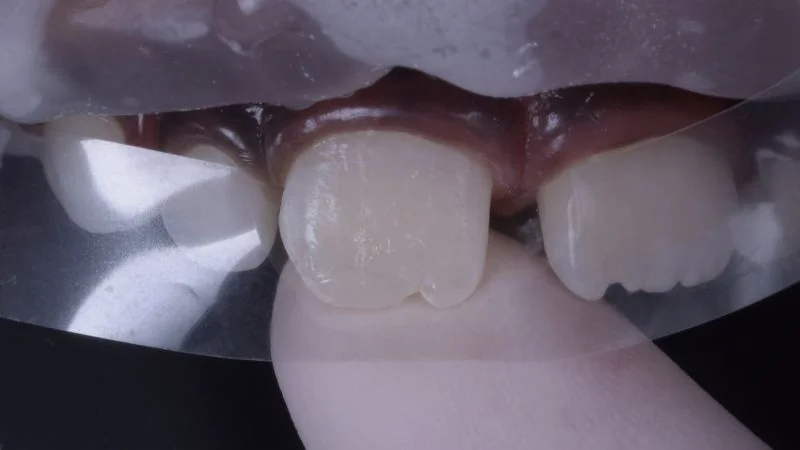

Restauration mit Komposit.

Freihand-Modellation der Komposit-Restauration.

Ausarbeitung und Politur.

Polierte Oberfläche der Restauration an Zahn 11. 3M Sof-Lex Ausarbeitungs- und Polierscheiben Medium, Fein, Superfein, Bimssteinpaste und Polierpaste kamen zum Einsatz. Die Ausformung der Inzisalkante erfolgte mit feinkörnigen rotierenden Instrumenten.